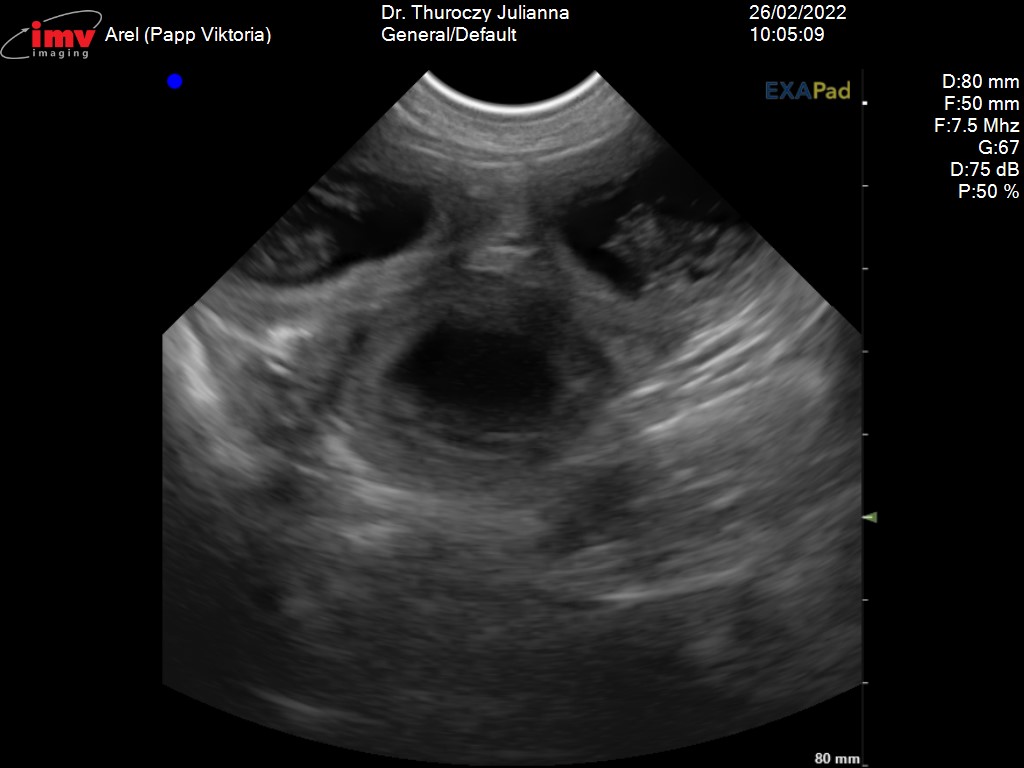

Az élet egyik nap elvesz a másik nap ad. A szombati ultrahang megerősítette hogy Arel és Beso pároztatása sikeres volt. Arel vemhes. Köszönjük Joanna a bizalmat. Gratulálunk Besónak, ügyes volt.